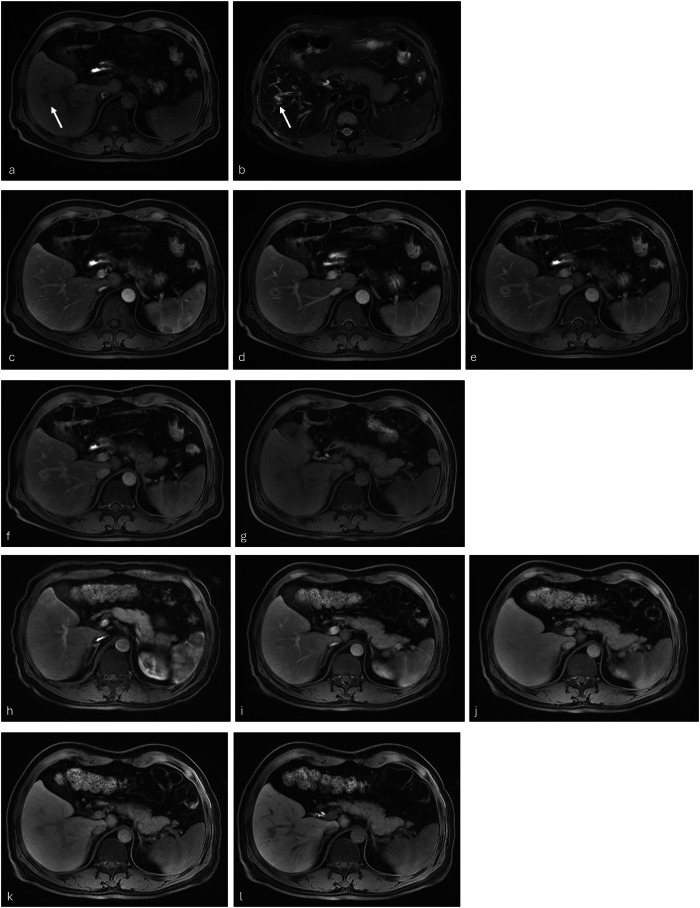

Abstract Image